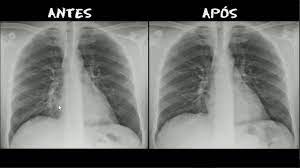

Pneumonia O Que E Causas Sintomas Tipos Tratamento Cura

Pneumonia O Que E Causas Sintomas Tipos Tratamento Cura from www.saudebemestar.pt

This illness can affect both children and adults. Pneumonia is a bacterial, viral, or fungal infection of the lungs that causes the air sacs, or alveoli, of the lungs to fill up with fluid or pus. Pneumonia este o infectie pulmonara obisnuita in care saculetii pneumatici ai plamanilor devin inflamati. Pneumonia can be generally defined as an infection of the lung parenchyma, in which consolidation of the sections bacterial pneumonia. Aceste saculete se pot umple, de asemenea, cu lichid, puroi si resturi. Learn about bacterial pneumonia causes, symptoms, the contagious period, treatments, and recovery time. Learn about causes, risk factors, prevention, signs and symptoms. Pneumonia por pneumocystis jirovecii 4.